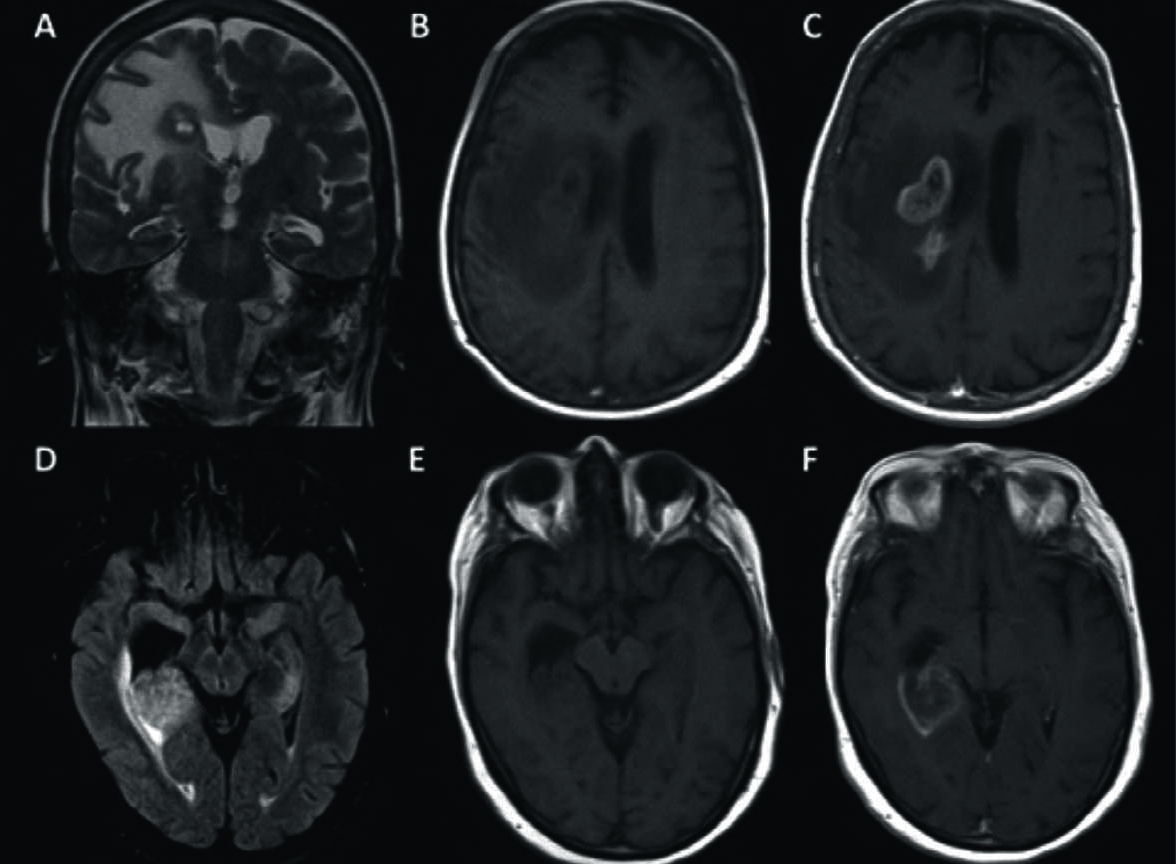

Figura 2

LPSN con lesión única de tronco encefálico (mesencéfalo).

Se identifica la lesión hipointensa en T1 (A) en el mesencéfalo, hiperintensa en T2 y FLAIR (B y C) con escaso edema, y fenómeno de restricción en difusión (D) y ADC (E). Con el medio de contraste (F) se observa el clásico patrón de realce intenso con borde irregulares.